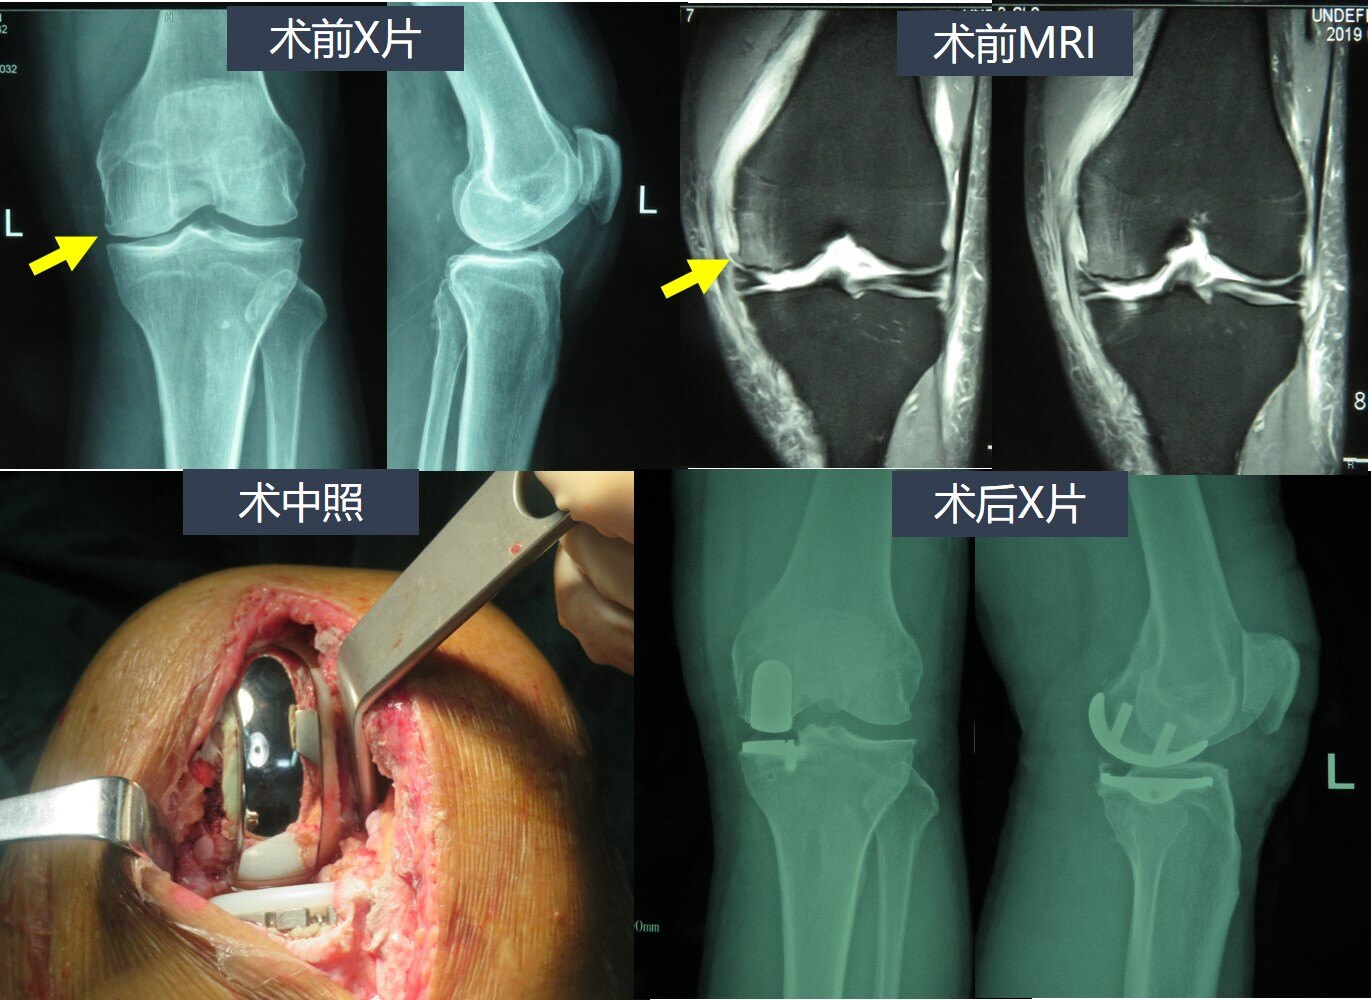

周末时间,帮助兴城市人民医院完成这例膝关节单髁置换手术,同时这也是

膝关节内侧单髁置换